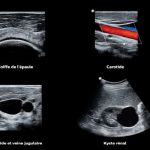

- Suitable for all major types of exams

- Quality imagery